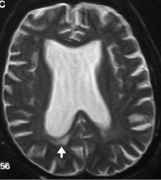

脑积水 ,是一种大脑和脊髓周围有额外的脑脊液的情况。脑脊液...

在产前发育过程中,大脑从管状结构开始。随着它的生长,内管...